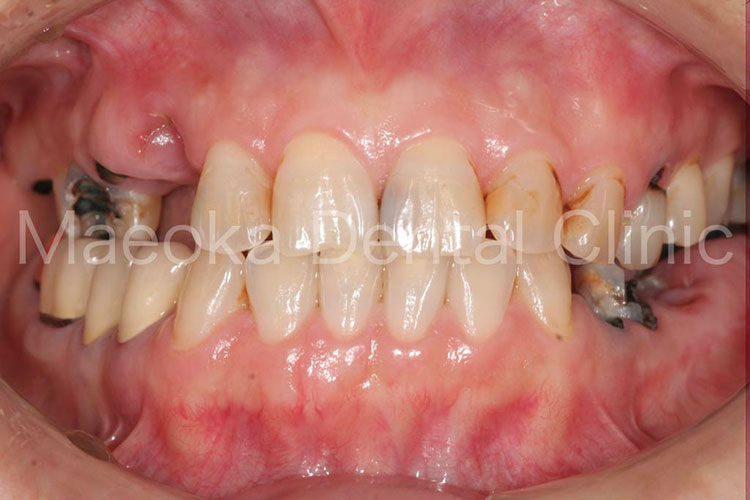

患者さんは54歳の女性の方で、「歯茎がすごく腫れているんですが、こんな口の中でも良くなりますか?」という主訴で来院されました。

初診の際には歯肉の腫脹と発赤が強く、右上には大きなサイナストラクト(歯肉にできた膿の出口)がありました。お話を伺うとご両親の介護で疲れ、なかなか自分の口の中までケアができていないということでした。

具体的な治療内容は治療を進める中で決めていくこととなり、先ずは現在のお口の中で一番の問題になっている歯周病の根本的な原因を取り除いていくところから治療をスタートしています。

患者さんの努力によって歯肉の状態が劇的に改善してきたタイミングで、不適切な被せ物をやり直すこととなりました。歯肉よりも上に健全な歯が残っていない箇所はExtrusion処置(歯を引っ張り出す処置)などを併用した上で、メタルセラミックスとゴールドクラウン、コンポジットレジンにて修復治療を終えています。

全体的な歯列不正(歯並びの乱れ)については、特に問題を生じていなかったため、現在のところ介入は不要と判断しています。

治療を通して患者さん自身のお口に対する意識が変わり、食生活も大きく改善されたことで長期的な安定が見込めるお口の環境になりました。

治療前(正面)